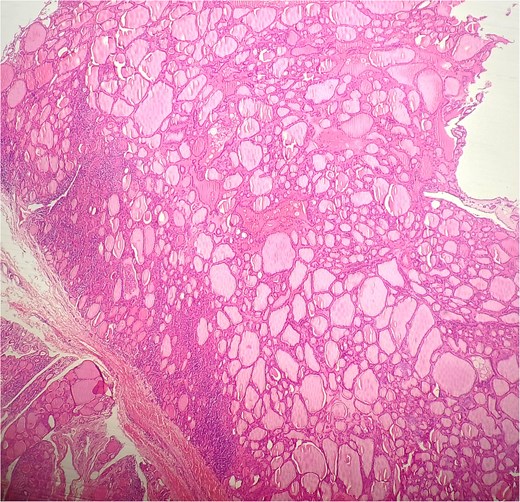

A 47-year-old woman with unremarkable medical history, presented with a 2 months history of neck mass along the midline. Physical examination revealed a 6 cm mobile, thyroid nodule without compressive symptoms. There was no associated erythema, fluctuance, tenderness or adhesion to adjacent structures. There was also no associated cervical lymphadenopathy. The rest of the physical exam was unremarkable. Laboratory tests including TSH, FT3, and FT4 revealed normal levels. On cervical ultrasound, there were a 62 mm left toto-lobar nodule classified as EU-TIRADS3, and an 11 mm right nodule, also classified as EU-TIRADS3. Fine-needle aspiration cytology concluded to a benign lesion classified as BETHESDA II. The patient reported respiratory discomfort in the supine position, leading to the indication for a lobectomy. Gross examination of the specimen revealed a toto-lobular nodule with a colloid appearance. It was well-circumscribed by a thin and regular fibrous capsule. The nodule measured 4 × 6 cm and exhibited areas of fibrous, whitish remodeling, as well as hemorrhagic and cystic changes. On microscopic examination, the nodule corresponded to a macro vesicular adenoma altered by fibrosis and hemorrhage. It was surrounded by a thin, regular, and intact fibrous capsule. However, at the periphery of the nodule, adjacent to the thyroid pseudo capsule, a 1.2 cm cystic ductal structure was observed. It showed pseudostratified ciliated columnar and squamous epithelial lining associated with thyroid follicles in the surrounding stroma (Figs 1 and 2). These thyroid follicles were bland with no papillary nuclear atypia or invasion (Fig. 3). The cyst was filled with a thin eosinophilic material (Fig. 4) Lymphocytic thyroiditis of mild severity was identified in the rest of the thyroid tissue. Based on these findings, the diagnosis of macro vesicular thyroid adenoma with ITTGDC and lymphocytic thyroiditis was made. After the surgery, the patient developed temporary dysphonia.

HE × 20: The cyst was lining with pseudostratified ciliated columnar cells and circumscribed with thyroid follicle within the cystic wall.